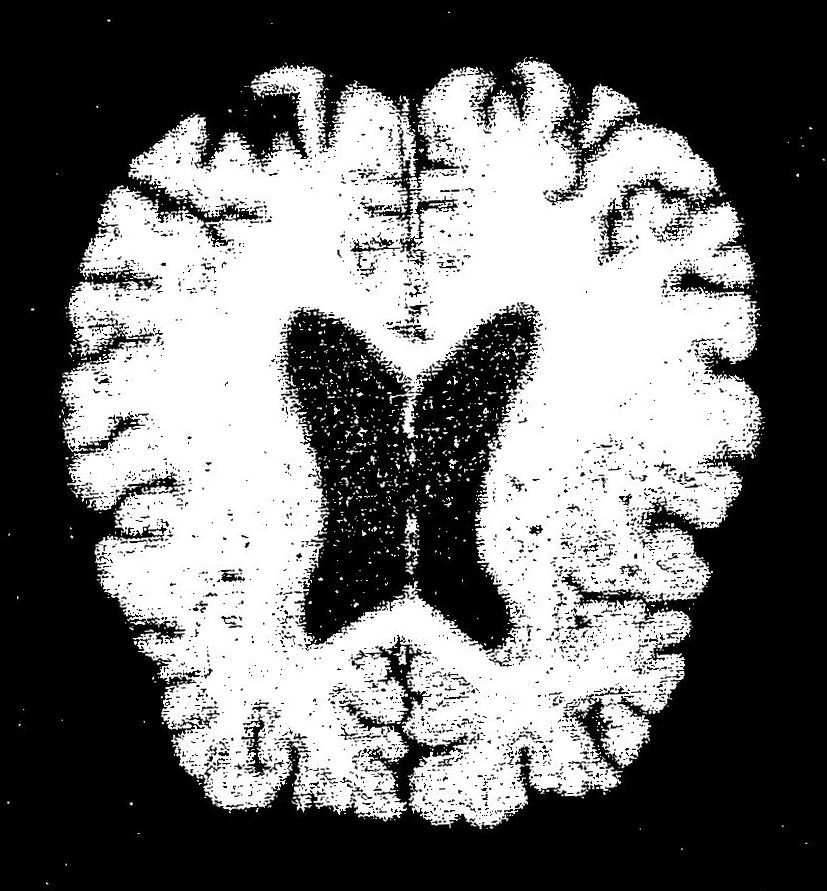

Souvenir picture of my brain from MRI performed Dec. 13, 2022 as part of my participation in the University of Wisconsin's SuperAging Study.